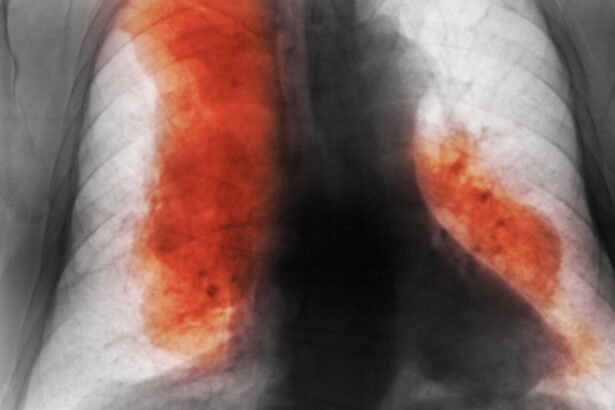

România, pe locul doi în Uniunea Europeană la decese evitabile…

Consumul ridicat de alcool și tutun în Europa Europa se…

```html Avertisment: România, pe primul loc în UE la decese…